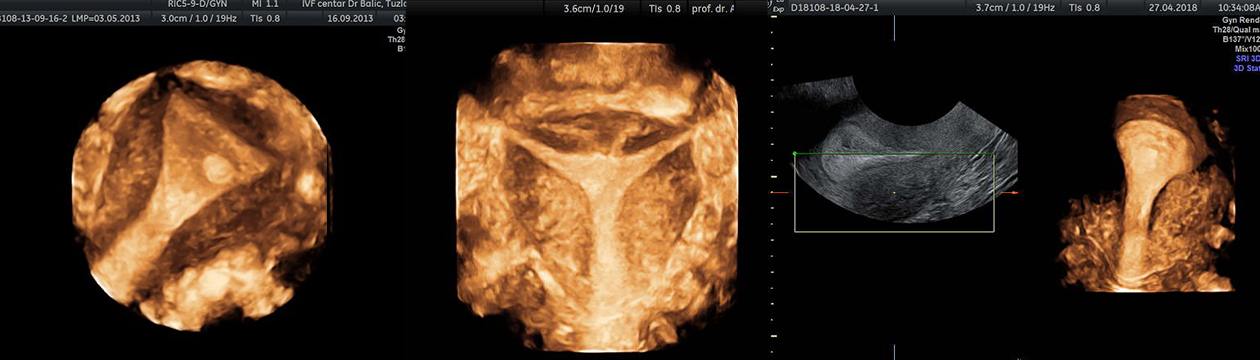

Ova vrsta ultrazvučnog pregleda omogućava vizualizaciju promatranih struktura u tri dimenzije. Ako se radi live 3D-u to znači da imamo trenutni trodimenzionalni prikaz promatrane strukture koji dalje možemo detaljno analizirati iz više uglova i sa svih strana. 4D (četverodimenzionalni ultrazvučni pregled) predstavlja trodimenzionalni prikaz u živo, te se zbog toga govori o tzv. “četvrtoj dimenziji”. Ovi pregled traje duže (i do pola sata) a mogu se obavljati vaginalnim putem ili preko stomaka. Ova tehnika omogućuje ne samo pregled površnih struktura nego i unutrašnjih organa daleko bolje nego i jedna druga tehnika, te može prikazati i krvne sudove u prostoru (3D power dopler) koji je nekim stanjima od posebne važnosti kao što tumori jajnika i miomatozni čvorovi.

Poseban značaj ovih pregleda u ginekologiji jeste zbog mogućnosti vrlo pouzdane procjene o obliku materišta (septum ili pregrada), otkrivanja polipa endometrija veličine samo par milimetara, te uvida u unutrašnjost cisti na jajnicima. Kad je u pitanju lokacija mioma u odnosu na materište, ovaj vid dijagnostike je suveren, s jedne strane što je pouzdan a s druge strane jer je brz i neinvazivan. Alternativa mu je jedino magnetna rezonanca koja ipak nije tako jednostavna i dostupna u rutinskoj dijagnostici.

Postoji više “modova” ili tehnika koje koje se koriste kod trodimenzionalnog ultrazvuka kao što su rendernig, VCI, VOCAL, sonoAVS, omni view, TUI koje nam pomažu da što preciznije procijenimo različite fiziološke i patološke promjene na genitalnim organima žene.